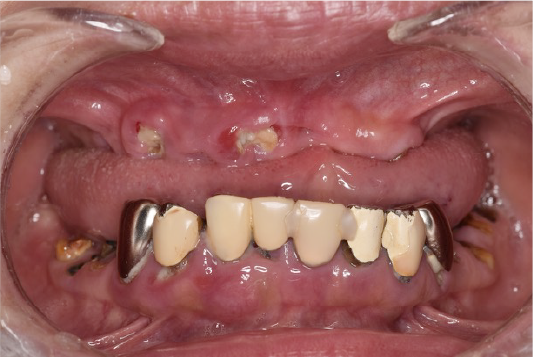

CASE01

■ 治療内容

上下顎All-on-4インプラント治療

■ 治療費用

7,438,000円(税込)

■ 治療期間

約10ヶ月

■ リスク

治療後の腫れや出血、またメンテナンスを怠ることで周囲炎のリスクあります。